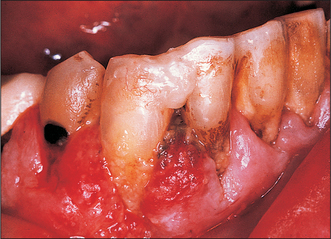

Gingiva and alveolar ridge (Fig. 10.9)

Carcinoma of the lower alveolar ridge occurs predominantly in the premolar and molar regions. The patient usually presents with proliferative tissue at the gingival margins or superficial gingival ulceration. Diagnosis is often delayed because a wide variety of inflammatory and reactive lesions occur in this region in association with the teeth or dentures (Fig. 10.9). Indeed, there will often be a history of tooth extraction with subsequent failure of the socket to heal before definitive diagnosis is made. Another common story is that of sudden difficulty in wearing dentures. Regional nodal metastasis is common at presentation, varying from 30 to 84%, although false-positive and false-negative clinical findings are common.

image

Fig. 10.9 Gingival carcinoma is often initially misdiagnosed as periodontal infection, as in this case.